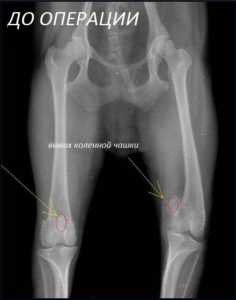

ВЫВИХ КОЛЕННОЙ ЧАШЕЧКИ.

Хотелось бы несколько рассказать Вам и привести пару примеров о такой патологии ,как вывих коленной чашечки(пателлярный вывих).

Вывих коленной чашечки может врожденным или травматическим по своему происхождению. Последний встречается у собак любой породы в результате удара по внешней(латеральной)поверхности коленного сустава, приводя к нестабильности и медиальному (во внутрь)коленной чашечки. Причина врожденного пателлярного вывиха не установлена. Заболевание чаще всего наблюдаетсяу небольших собак, таких, как карликовый и той пудель, йоркширсий терьер, чихуахуа, грифон, шпиц.Однако оно встречается и у собак более крупных пород.У кошек встречается это заболевание:либо врожденное,когда оно часто бывает бессимптомным,либо в сочетании с вывихом тазобедренного сустава.У собак с застралым бессимптомным вывихом может появится хромота в результате повреждения крестовидной связки. При лечении подобых случаев пателлярный вывих будет иметь большое значение,чем вторичное повреждение крестовидной связки, конечно в зависимости от размера собаки.

.ЗАКЛЮЧЕНИЕ Таким образом вывих коленной чашечки частое явление для животных,и более чем часто у карликовых пород собак. При проявлении хромоты ,беспокойства у Ваших питомцев рекомендуем вызвать ортопеда вызывной службы ЛЬВЕНОК-для постановки диагноза и назначения адекватного лечения.